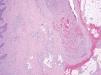

Las malformaciones venosas están constituidas por vasos ectásicos de tamaño variable, que asientan en la dermis profunda y tejido celular subcutáneo. Algunos son de pared fina, mientras que otros presentan una capa muscular gruesa. Es frecuente la presencia de trombosis y flebolitos, así como el hallazgo de áreas de hemorragia con depósitos de hemosiderina y calcificaciones extravasculares (fig. 10).

Figura 10. Vasos ectásicos de pared fina en dermis profunda correspondientes a malformación venosa. Hematoxilina-eosina, x100.